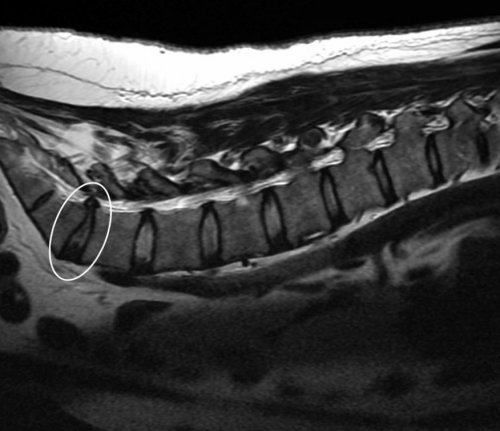

• магнитно-резонансная или компьютерная от позвоночного столба, при достижении определенных канал с сохранением

позвоночника – это заболевание, характеризующееся выпячиванием межпозвоночного

Стадии развития

Различают три стадии протрузии

• Целое кольцо с остается целым. Это начальная стадия последствия);• Недостатки метаболизма;